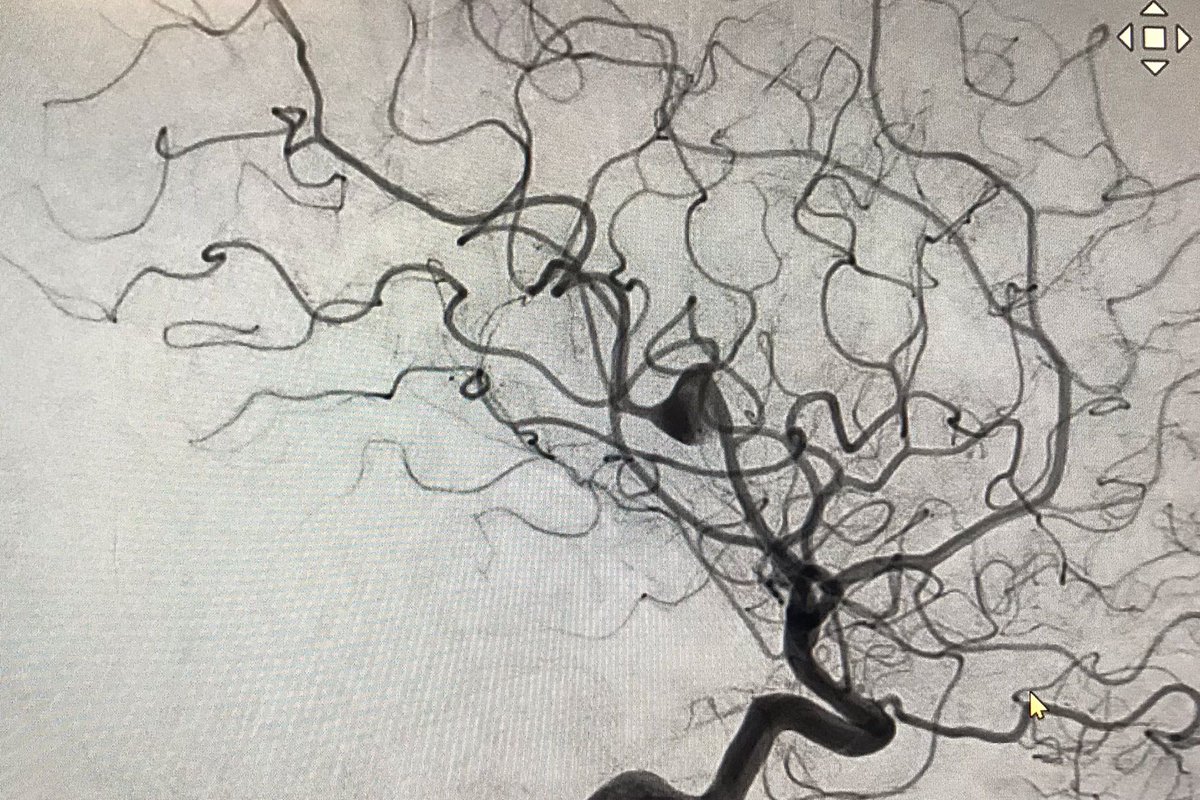

El Dr. Carlos Pérez@Justcharly9, nos resume en menos de 15 minutos los dos principales ensayos clínicos que comparan tratamiento Endovascular VS Quirúrgico (ISAT, IBRAT) de aneurismas rotos.